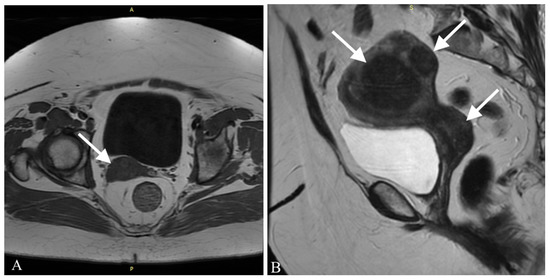

The patient underwent a surgical procedure of excising the polyp at its peduncle using a LEEP loop electrode. It could not be removed in one piece—the polyp fragmented into several pieces during extraction. Then, a curettage of the cervix and an unsuccessful attempt of a uterine cavity curettage was performed. Obtained tissues were then sent to the pathology department for a histopathological examination. The findings were ready in six weeks after the procedure and revealed the presence of rhabdomyosarcoma embryonale (type botryoides) in the excised polyp. Due to the fact that the polyp was fragmented during extraction, a precise margin status or the depth of invasion could not be properly determined. Histopathological images are presented in Figure 1.

Post-menopausal hemorrhaging is, on the other hand, a common symptom, affecting almost 1 in 10 women worldwide. Out of all these cases, 10% are caused by neoplasms [14]. As other studies show, vaginal bleeding is also the most common symptom in RMS of the genitourinary tract. Other symptoms include abdominal and lower pelvic pain or frequent urination [9]. When dealing with patients complaining about abnormal vaginal bleeding, a careful approach is advised. Performing a histopathological examination of the tissues collected from uterine curettage is necessary, because it can allow us to diagnose even such uncommon problems as ERMS. Histopathological evaluation of the excised material is often a complicated task when dealing with sarcomas. The reason for that is the fact that sarcomas present a very diverse image. Embryonal rhabdomyosarcoma usually presents a few traits: agglomerations of spindle and round pleomorphic cells with hyperchromatic nuclei, rhabdomyoblasts and myxoid stroma [9,10,11]. Performing an immunohistochemical profile of the tissue is nowadays a must in diagnosing sarcomas. In the case of rhabdomyosarcoma, staining for myoglobin, desmin and muscle-specific actin is observed. The most sensitive and specific RMS markers are myogenin and Myo-D1, proteins characteristic for early differentiation of muscle cells, and they often prove to be the key traits in making the final diagnosis [15,16]. In our case, the immunohistochemistry showed positive CD10, myogenin and desmin and negative SMA, ER, PR and S100 markers. These results, combined with microscopic description, allowed us to perform differential diagnosis and rule out more common out neoplasms occurring more frequently, such as the leiomyosarcoma or adeno-sarcoma, as well as identify a specific subtype of RMS—rhabdomyosarcoma embryonale botryoides in this case.

Figure 1. Histopathological images of the excised polyp (A) in 10× magnification. (B) in 20× magnification. Arrows show spindle and round pleomorphic cells with hyperchromatic nuclei and scant cytoplasm.